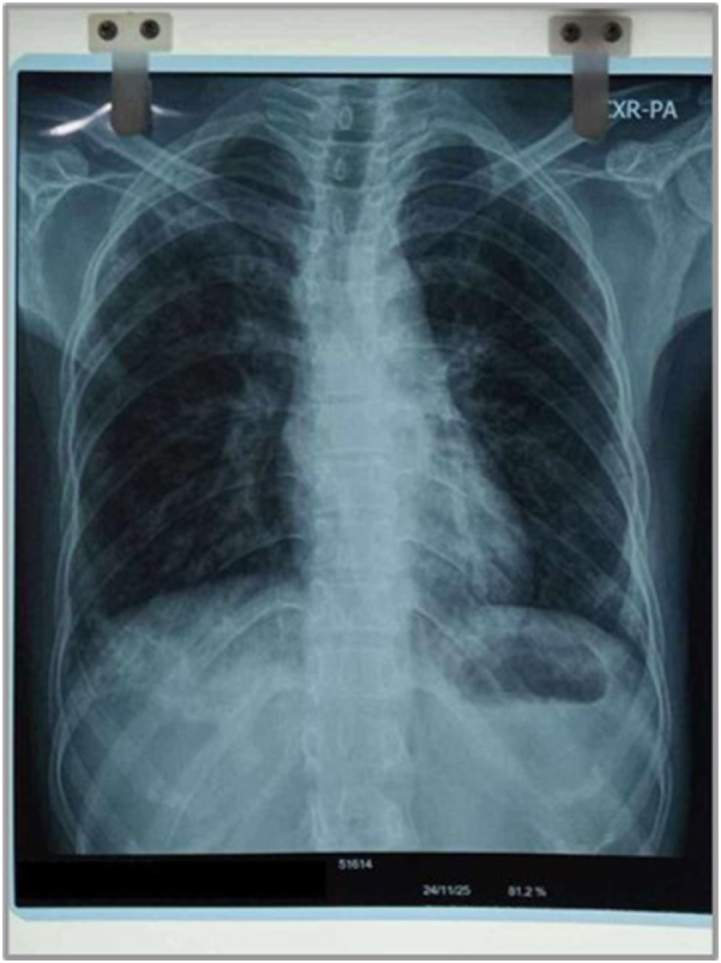

Case presentation: A 27-year-old woman receiving treatment for pulmonary tuberculosis presented to us with worsening joint pain, swelling, facial rash, and muscle weakness. She had trouble with basic movements like climbing stairs and noticed rashes over her face and knuckles. On examination, she had a malar rash and Gottron's papules, with noticeably weakness in her upper and lower limbs. Her lab results showed elevated ESR and a positive PM-Scl antibody; meanwhile, other autoimmune markers were negative. Her imaging revealed tenosynovitis and microvascular changes on capillaroscopy. She was then diagnosed with undifferentiated inflammatory arthritis, within the myositis spectrum - and was started on steroids and DMARDs while continuing her TB therapy.